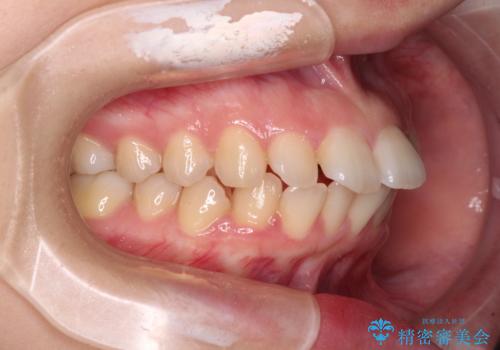

- 上下の前歯が突出しており、口が閉じにくいとのことで来院された患者様です。

上下前歯が著しく前突している状態であったので、上下左右の第1小臼歯4本を抜歯し、ワイヤー装置にて矯正治療を行うこととしました。

舌の突出癖により、前突になったと考えられたため、舌のトレーニングをしっかりと行うよう指導しました。